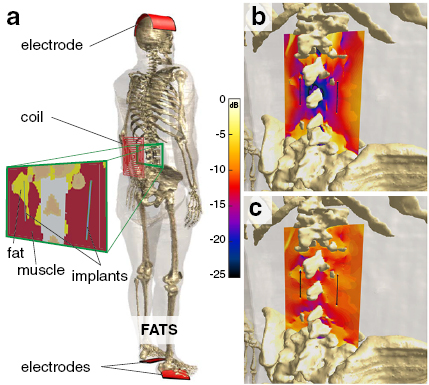

2.2.3. In vivo exposure

To confirm the validity of the model in realistic inhomogeneous setups, simulations involving detailed anatomical models and a realistic implant were performed. The male adult human computational anatomical model 'Fats' from the Virtual Population (ViP) (Gosselin et al 2014) was used in combination with the model of an abandoned neuro-stimulator lead shown in figure 1. It features an insulated helical wire structure embedded in additional insulating material around an air-filled core. One end consists of a large and rounded electrode and the other ('tail') is the cut lead with only a small cross-section of the wire exposed. The implant models were positioned on the left and right of the spine, based on medical images of a patient. The right one was completely embedded in muscle, while the left one was partly in muscle (tail) and partly in fat (electrode). In all cases, the tissue environment was inhomogeneous, involving tissue interfaces with high dielectric contrast (e.g. to bone) in implant proximity. Exposure to E and magnetic (B) fields was simulated (figure 6). The B-field originated from a 10-turn rectangular spirangle coil, while electric exposure was to a capacitively-applied, longitudinally-oriented E-field. Tissue dielectric properties were assigned according to published values for exposure at 100 kHz (Hasgall et al 2016). Simulations were performed with the magneto-quasistatic and the ohmic-current dominated EQS solvers on a mesh with body resolution of 2 mm, refinement of 0.5 mm in the tip regions, and refinement of 0.03 mm of the wire and insulation. To determine  and

and  (see section 2.1), two simulations were performed: homogeneous implant exposure within a homogeneous medium (0.5 S m−1) and semi-homogeneous exposure within two half-spaces (0.5 S m−1 and 0.1 S m−1). For the semi-homogeneous exposure the electrode was embedded in the 0.5 S m−1 medium and the tail in the 0.1 S m−1 medium. From these two simulations, in vivo J and psSAR at the electrodes and tails of the left and right implant were estimated, using the mechanistic model and computed incident field conditions from electric and magnetic exposure in the absence of implants. For additional validation, another semi-homogeneous exposure simulation with inverted implant orientation was performed and compared to the model predictions.

(see section 2.1), two simulations were performed: homogeneous implant exposure within a homogeneous medium (0.5 S m−1) and semi-homogeneous exposure within two half-spaces (0.5 S m−1 and 0.1 S m−1). For the semi-homogeneous exposure the electrode was embedded in the 0.5 S m−1 medium and the tail in the 0.1 S m−1 medium. From these two simulations, in vivo J and psSAR at the electrodes and tails of the left and right implant were estimated, using the mechanistic model and computed incident field conditions from electric and magnetic exposure in the absence of implants. For additional validation, another semi-homogeneous exposure simulation with inverted implant orientation was performed and compared to the model predictions.

Figure 6. Setup for the validation of the mechanistic model involving exposure of the detailed human ViP anatomical model Fats with integrated implants to a coil-sourced B-field or to a capacitively applied E-field (a). Illustrative E-field distributions are shown for the magnetic (b) and electric (c) exposures.

Download figure:

3.3. Exposure in an anatomical environment

To validate the model proposed in section 2.1 in complex, inhomogeneous body environments (as relevant for safety assessments), simulated implant-related energy depositions and field enhancements at the two ends (electrode and cut lead tail) of abandoned neuro-stimulator leads near the spine of an anatomical model under electric and magnetic exposure (see section 2.2.3) were compared to predictions from the proposed model. Those predictions were derived by combining (i) characterization of the electrode and tail behavior in two simple and (semi-)homogeneous environment and exposure conditions (to determine  and

and  ; see sections 2.1 and 2.2), (ii) information about the tissue conductivities at the electrode and tail locations (right implant: muscle conductivity at both ends; left implant: fat conductivity at the electrode and muscle conductivity at the tail), and (iii) the integrated tangential incident in vivo fields, according to equation (4). (i) revealed that

; see sections 2.1 and 2.2), (ii) information about the tissue conductivities at the electrode and tail locations (right implant: muscle conductivity at both ends; left implant: fat conductivity at the electrode and muscle conductivity at the tail), and (iii) the integrated tangential incident in vivo fields, according to equation (4). (i) revealed that  is 30 times larger than

is 30 times larger than  , due to the reduced resistance to current entering the large electrode compared to the resistance of entering the small exposed wire cross-section of the cut lead. The psSAR

, due to the reduced resistance to current entering the large electrode compared to the resistance of entering the small exposed wire cross-section of the cut lead. The psSAR , psSAR

, psSAR , and psSAR

, and psSAR at the two implant ends, for electric and magnetic exposure, and for the two anatomical implant placements show an averaged signed deviation from the numerically obtained reference values of 0.1% (i.e. there is no systematic bias), a coefficient of variation of 7%, and a maximal deviation of 15%, thus supporting the proposed mechanistic model and demonstrating its predictive value.

at the two implant ends, for electric and magnetic exposure, and for the two anatomical implant placements show an averaged signed deviation from the numerically obtained reference values of 0.1% (i.e. there is no systematic bias), a coefficient of variation of 7%, and a maximal deviation of 15%, thus supporting the proposed mechanistic model and demonstrating its predictive value.